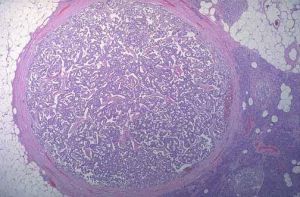

4.套用免疫組織化學方法測定腫瘤中的激素,腫瘤組織中胰多肽含量顯著增高,其他胰腺內分泌激素很少,為本病的重要依據之一。